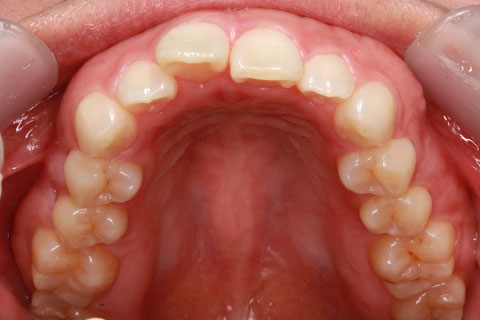

ハーフリンガル矯正3:上の歯のみ舌側矯正で治療(矯正期間24ヶ月)

治療中(開始半年後)

- 年齢・性別

- 25歳女性

- 治療期間

- 2年0ヶ月

- 抜歯

- 上下4番抜歯

- 治療費

- 110万円

- 治療内容

- 施術の副作用(リスク)

- 表側矯正と比較して、力学的な操作性が複雑なため、ボーイングエフェクトを起こしやすい。